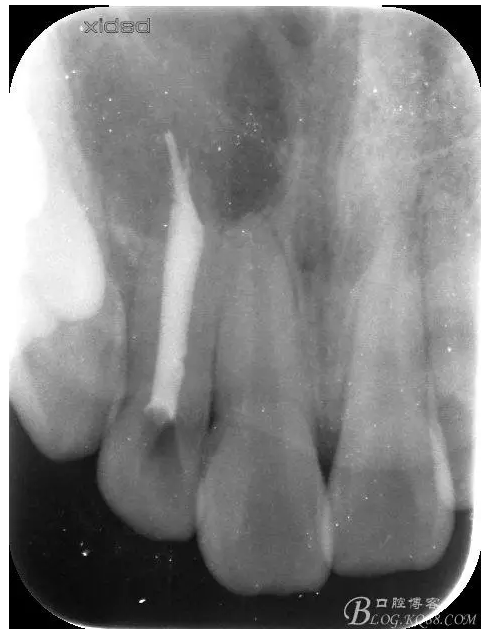

圖3.依缺損部位為中心,逐漸去骨,完整暴露出囊壁。

圖4.摘除囊壁后形成的巨大骨腔

圖5.清理骨腔,可以看到12的根尖暴露在骨腔內(nèi)。

圖6.超聲骨刀切除根尖3mm。